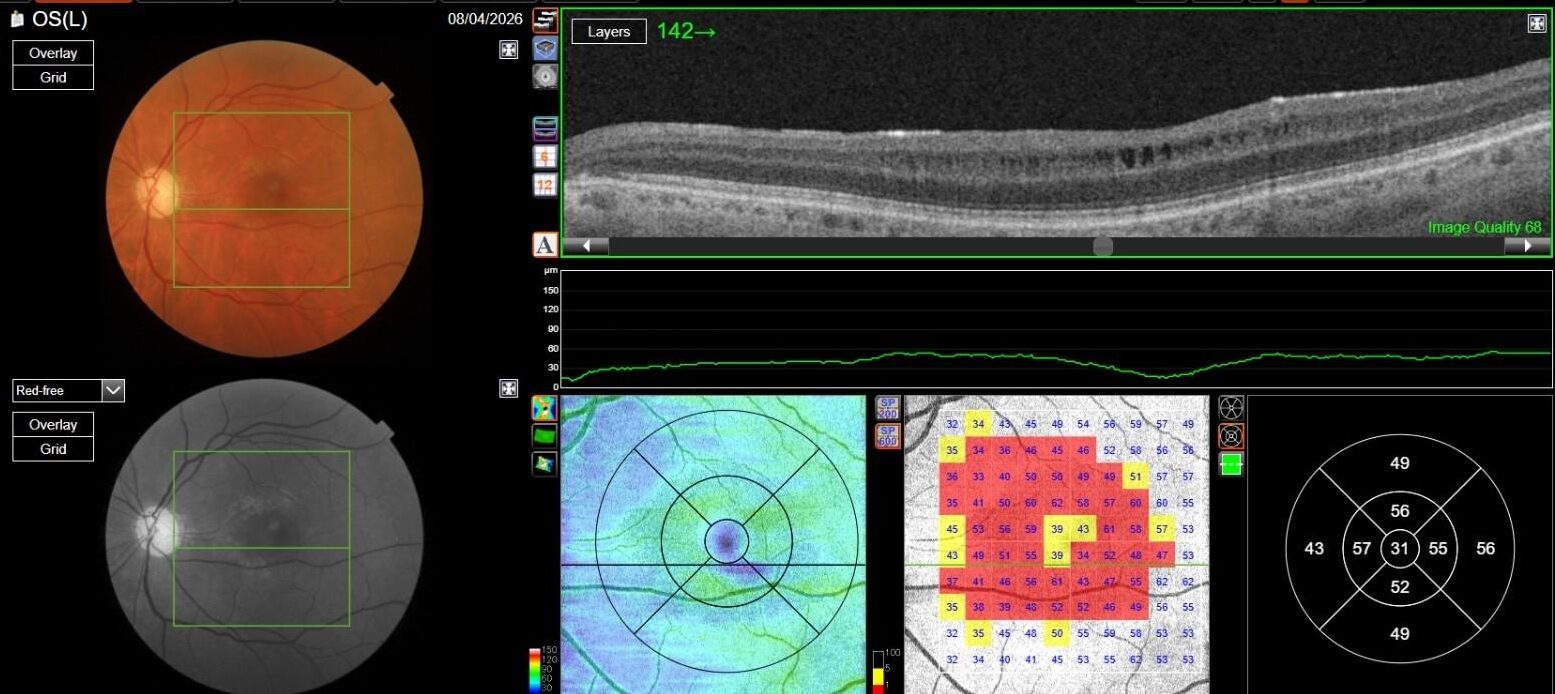

OCT in OD was normal, while in OS it showed multiple, well-defined small hyporeflective cystic spaces localized to the inner retinal layer (INL) in the perifoveal area, alongside with extreme thinning of the retinal nerve fiber layer (RNFL), whose profile and reflectivity were barely noticeable.

OCT-A was also performed in OS and, as expected, turned out to be negative. This also allowed an OCT en-face acquisition and subsequent segmentation at INL, which clearly showed the perifoveal distribution pattern of the INL cystic spaces previously found on b-scan OCT, with complete encompassing of the fovea and relative predominance in the inferior macular region.